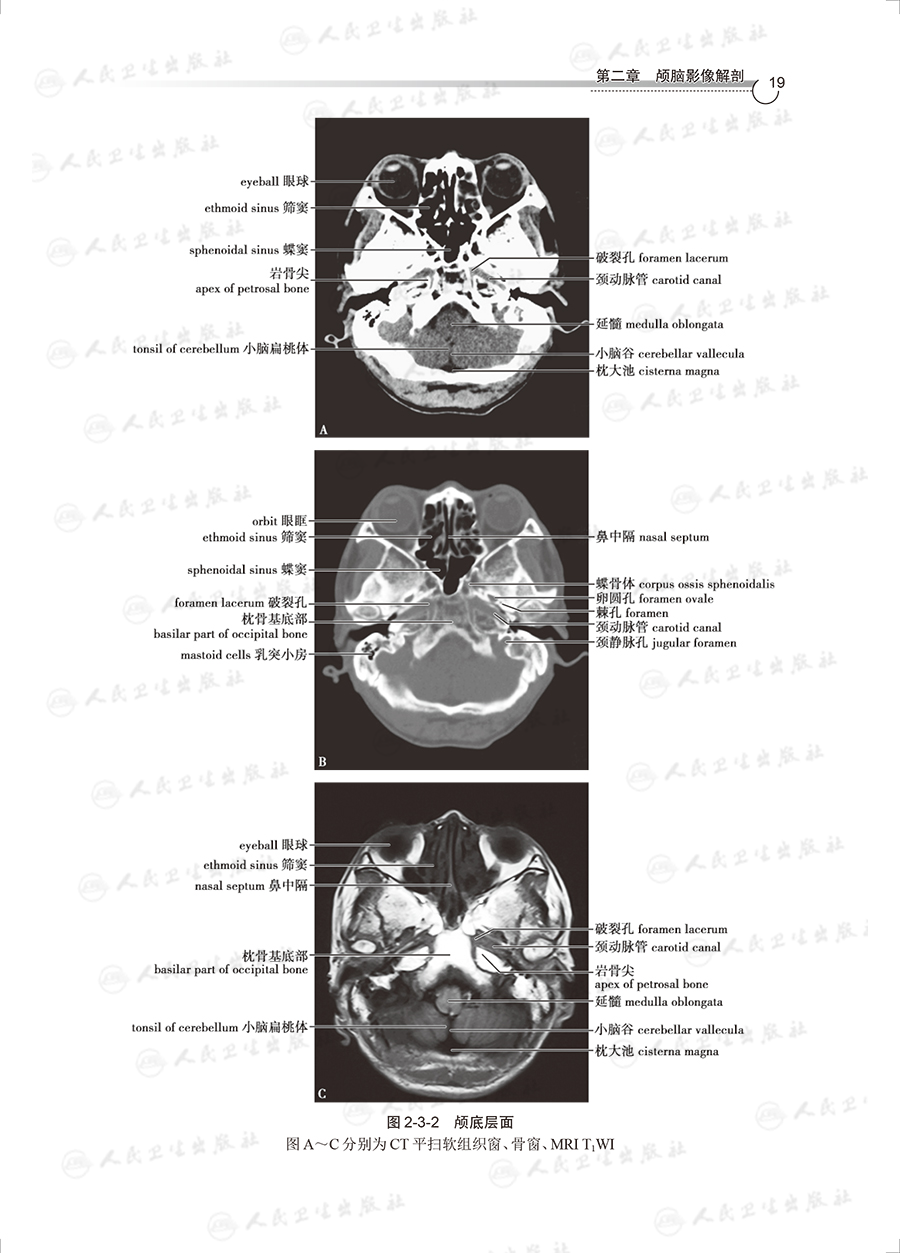

全书分为总论、颅脑、颜面部、颈部、胸部、腹部等9章,以临床应用为导向,对重要知识点加以拓展和延伸,激发学生的学习兴趣。除纸质版教材外,还提供了增值服务,各章节配备了近60个重要知识点短视频,学生可扫码观看学习。每章的自测题,类型多种多样,将影像解剖知识与影像诊断临床实践相结合,便于学生有的放矢,学以致用。